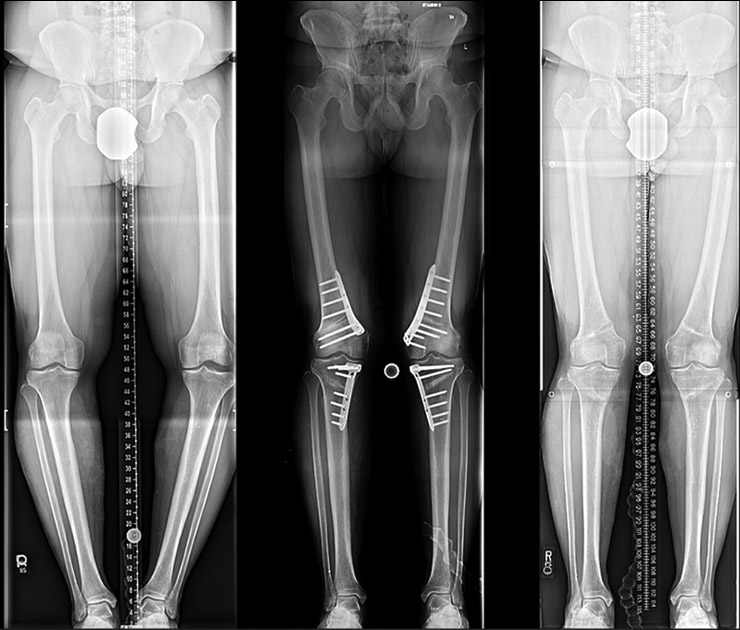

- Surgery: In severe cases, surgical procedures like guided growth (temporary hemiepiphysiodesis) or corrective osteotomy may be necessary to realign the bones

- Diagnosis and Assessment: Accurately diagnosing the condition and assessing its severity using clinical examinations and imaging studies.

- Surgical Intervention: Performing surgical procedures when necessary to correct the deformity and restore proper alignment.